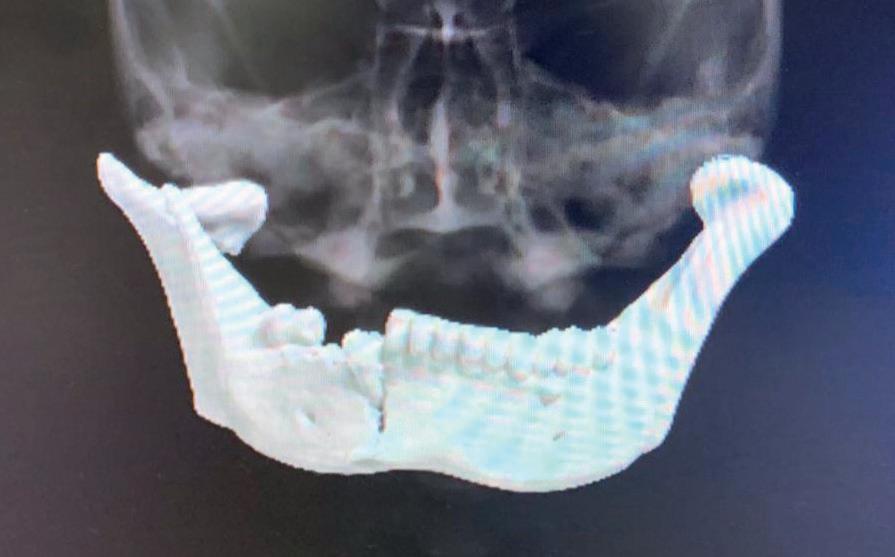

Door middel van AI in DTX Studio worden focusgebieden gemarkeerd op intraorale röntgenbeelden voor tandheelkundige bevindingen, zoals cariës, apicale laesie, wortelkanaaldefect, marginaal defect, botverlies en calculus (tandsteen). Uiteraard dient dit focusgebied door de behandelaar te worden gecontroleerd om tot een diagnose te komen. Het voorstel van de software zal dan worden gevalideerd dan wel worden afgewezen door de behandelaar. Ook wordt er steeds meer gebruik gemaakt van Guided Surgery en bij het vervaardigen van de proefopstelling en de implantaat planning speelt AI een steeds belangrijkere rol. Daar waar voorheen het laboratorium te extraheren elementen moest raderen en een set-up vervaardigen, kan dit inmiddels ook in de planningssoftware. Met deze planning kan guided met een boormal of door middel van navigatie worden geïmplanteerd, maar ook als er freehand wordt gewerkt, wordt er meestal vooraf een 3D-planning vervaardigd.”

Na vier maanden wordt er een CBCT gemaakt om het botvolume te kunnen beoordelen en een digitale planning te kunnen maken voor het plaatsen van het implantaat. Tevens wordt de stabiliteit van de botpieken op het buurelementen bekeken (foto 15 en 16).